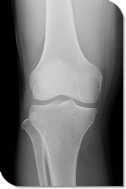

一般撮影

胸部や腹部、手や足などの全身のX線写真を撮影しています。 当院では、コンピューテッドラジオグラフィーによる撮影を行っています。 撮影を行った画像はコンピュータにより処理され、PACSと呼ばれるシステムに保存されます。

患者様のX線写真は、従来のフィルムだけでなく画像データとしても保存しています。 そのため各診療科および病棟の端末からからだけでなく、臼杵市内の会員の施設でもリアルタイムに観察可能です。